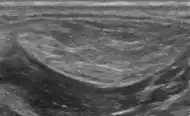

Ultrasonography of a liposarcoma for comparison: In this case a heterogeneous mass consisting of an upper hyperechoic portion, corresponding to lipomatous matrix, and areas of hypoechogenicity corresponding to nonlipomatous components.[24]

Ultrasonography of a liposarcoma mimicking lipoma. A homogeneous hypoechoic mass presenting with the same appearance of lipoma. It was clinically distinguished by having rapid growth.[24]